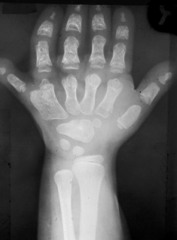

trisomy 13

Front

-extra chromosome 13 -bilateral cleft lip and palate, polydactyly, microphthalmia

Turner syndrome

-one X chromosome missing in women -short stature, webbing of neck, edema of hands